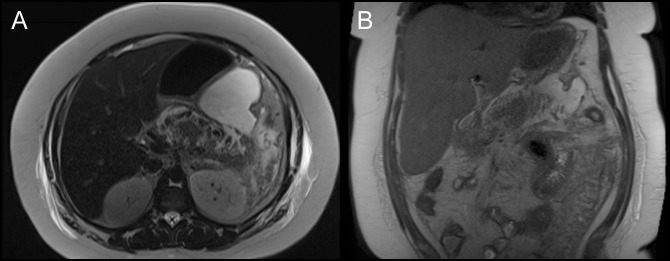

Figure 2.

Magnetic resonance cholangiopancreatography in (A) axial and (B) coronal views obtained on day 10 of admission. Hemorrhagic and acute necrotizing pancreatic and peripancreatic fluid collections visualized, predominantly affecting body and tail of pancreas.